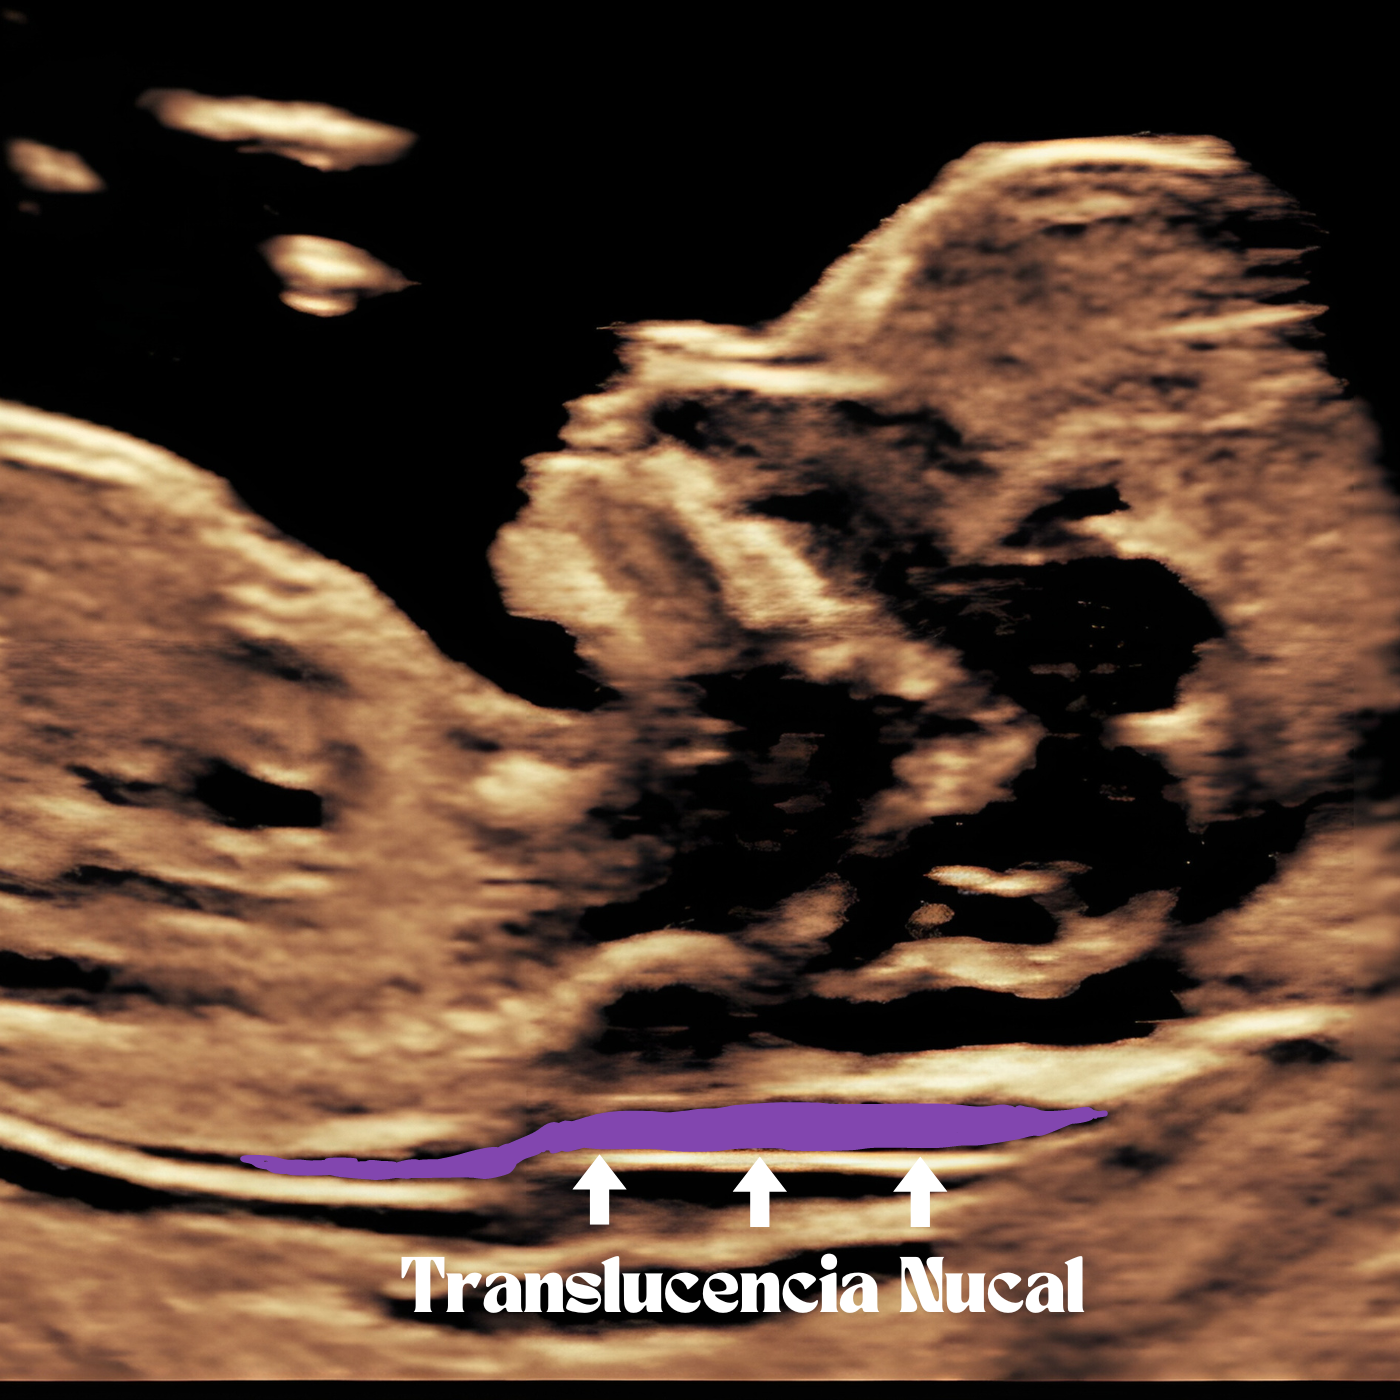

La ecografía genética, también conocida como ecografía del primer trimestre, es una herramienta crucial en el campo de la medicina prenatal. Esta prueba no invasiva utiliza la tecnología de ultraso...